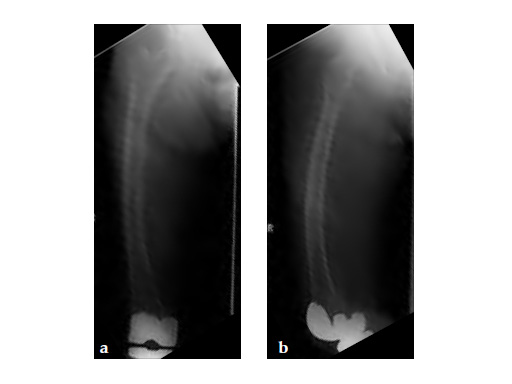

Three weeks prior to her last admission, she complains of recurrent right thigh pain for which epidural analgesics were administered for presumed radiculopathy, however preliminary x-rays and even MRI of the thigh were also taken in view of her primary complaint regarding her right thigh. These investigations did not indicate the possibility of impending bisphosphonate related femur fracture. It is clear from the radiographs that she has an obvious anterolateral bow of her femur and a thickened lateral cortex in the lateral midshaft cortical bone, which may indicate a stress fracture (see Fig 3a-b).